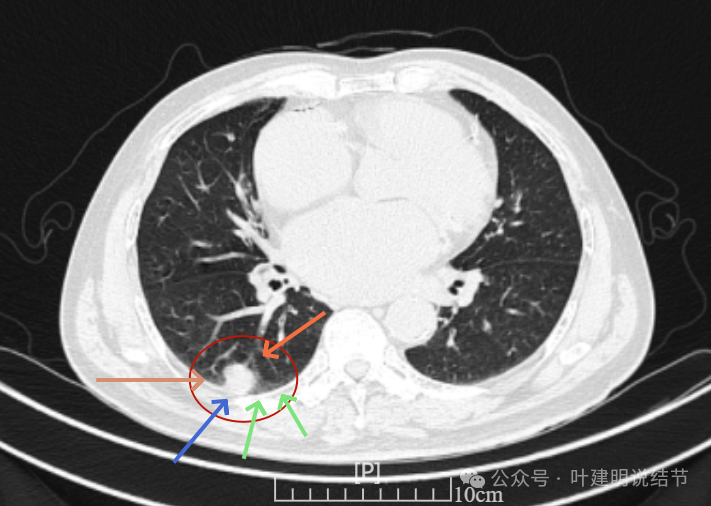

病灶有血管进入,有浅分叶,实性为主,邻近胸膜有片状淡磨玻璃影,近胸膜无牵拉。但有一定膨胀性。

病灶实性,与血管关系较为密切。

血管走向病灶,但似乎没有被病灶影响,有向内侧的分支甚至没有哪怕一点凹向病灶侧。整体显得偏模糊。

边缘区域杂乱,边糊。

这是冠状位、矢状位与轴位的影像。

增强纵隔窗见病灶内部的密度好像低于周围区域,像坏死。

邻近胸膜无牵拉,灶内有低密度区,局部有点状液性密度。邻近胸膜较为广泛的增厚或胸膜反应。

病灶与胸膜接触面宽,病灶内部密度较低。